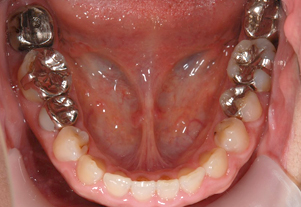

症例1

Before

After

- POINT

- 20代前半の患者様です。年齢が若くても歯周病、歯肉炎は発症してしまいます。ホームケアの指導と治療の説明をしっかり行い、専門家によって丁寧に歯石を除去することで、健康な歯茎を取り戻しました。前歯の厚い歯茎は歯茎の形態を整える手術をしています。すべて保険治療です。